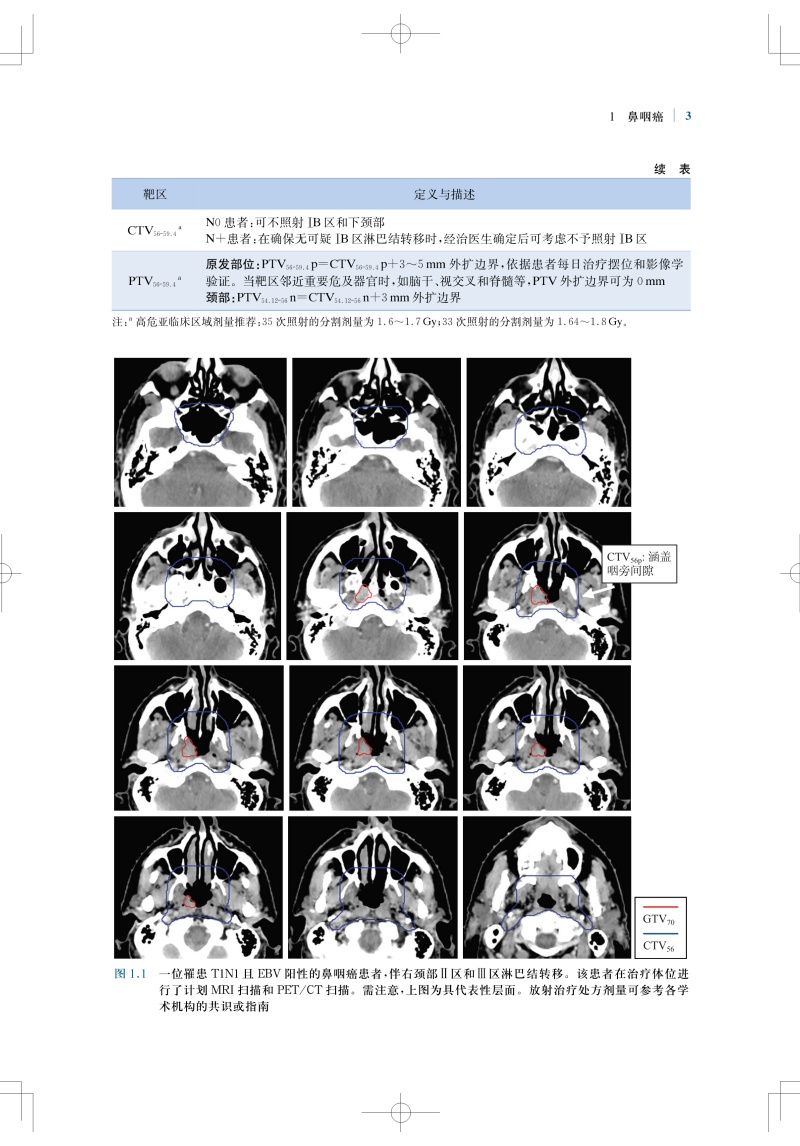

肿瘤放射治疗靶区勾画与射野设置是疗效的基石,精准的靶区范围的确定和勾画可确保肿瘤患者的放疗效果。全书结合大量影像图片,按章分别详细介绍了各种常见病变的具有临床依据的精确的CTV勾画和指南,包括鼻咽癌、甲状腺癌、早期乳腺癌、肺癌、直肠癌、前列腺腺癌、膀胱癌等;并对相关的淋巴引流区解剖进行了勾画,且逐层显示并说明注意事项。本书内容实用,可为放疗医师对常见肿瘤进行适形放疗和调强放疗时的靶区勾画及放射野设置提供指导和参考。